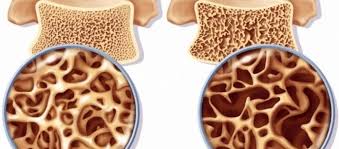

A osteoporose é uma patologia que acelera a perda de massa óssea, deixando os ossos mais frágeis e porosos. Ela costuma surgir na terceira idade e provoca a diminuição da absorção de minerais e de cálcio. Com isso, os riscos de fraturas aumentam, principalmente no quadril, costela e colo do fêmur. De acordo com a Fundação Internacional da Osteoporose, a doença atinge 10 milhões de brasileiros e deve crescer 32% até 2050 no país.

VERDADE. A maioria dos casos de osteoporose só é diagnosticada após a fratura, porque não apresentam sintomas. Por isso, é necessária a investigação com densitometria óssea durante os exames anuais para tratarmos preventivamente.